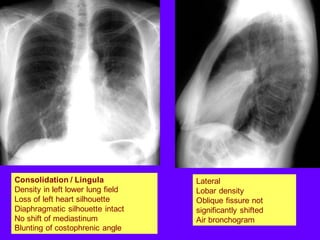

Consolidation / Lingula

Density in left lower lung field

Loss of left heart silhouette

Diaphragmatic silhouette intact

No shift of mediastinum

Blunting of costophrenic angle

Lateral

Lobar density

Oblique fissure not

significantly shifted

Air bronchogram